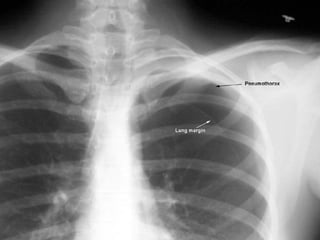

Pulmonary function tests  are weakly sensitive measures of the presence or size of pneumothorax and are not recommended   . Arterial blood gas measurements  are frequently abnormal in patients with pneumothorax with the arterial oxygen tension (PaO2) being less than 10.9 kPa (80 mm Hg) . In both primary and secondary spontaneous pneumothorax the diagnosis is normally established by  plain chest x ray . Expiratory chest radiographs  are not recommended for the routine diagnosis of pneumothorax   .

SIZE OF PNEUMOTHORAX The size of a pneumothorax, in terms of volume, is difficult to assess accurately from a chest radiograph which is a two dimensional image.  In the 1993 guidelines pneumothorax were classified into three groups: •  “ Small” :  defined as a “small rim of air around the lung” . •  “ Moderate” :  defined as lung “collapsed halfway towards the heart border” •  “ Complete” :  defined as “airless lung, separate from the  diaphragm .

The volume of a pneumothorax approximates to the  ratio   of the cube of the of the lung diameter to the hemithorax diameter . A pneumothorax of  1 cm  on the PA chest radiograph occupies about  27%  of the hemithorax volume if the lung is 9 cm in diameter and the hemithorax 10 cm:  (10 3  – 9 3 )/10 3  = 27%.  A  2 cm  radiographic pneumothorax occupies  49%  of the hemithorax on the same basis .

Volume of pneumothorax (12 3  -  9.5 3 ) /12 3  = 50% Tx suggested  :  Intercostal tube drainage 9.5 cm 12 cm

The previous classification of the size of a pneumothorax  tends to underestimate its volume.  In these new guidelines the size of a pneumothorax is divided into  “small” or “large”  depending on the presence of a visible rim of  <2 cm or >2 cm  between the lung margin and the chest wall .